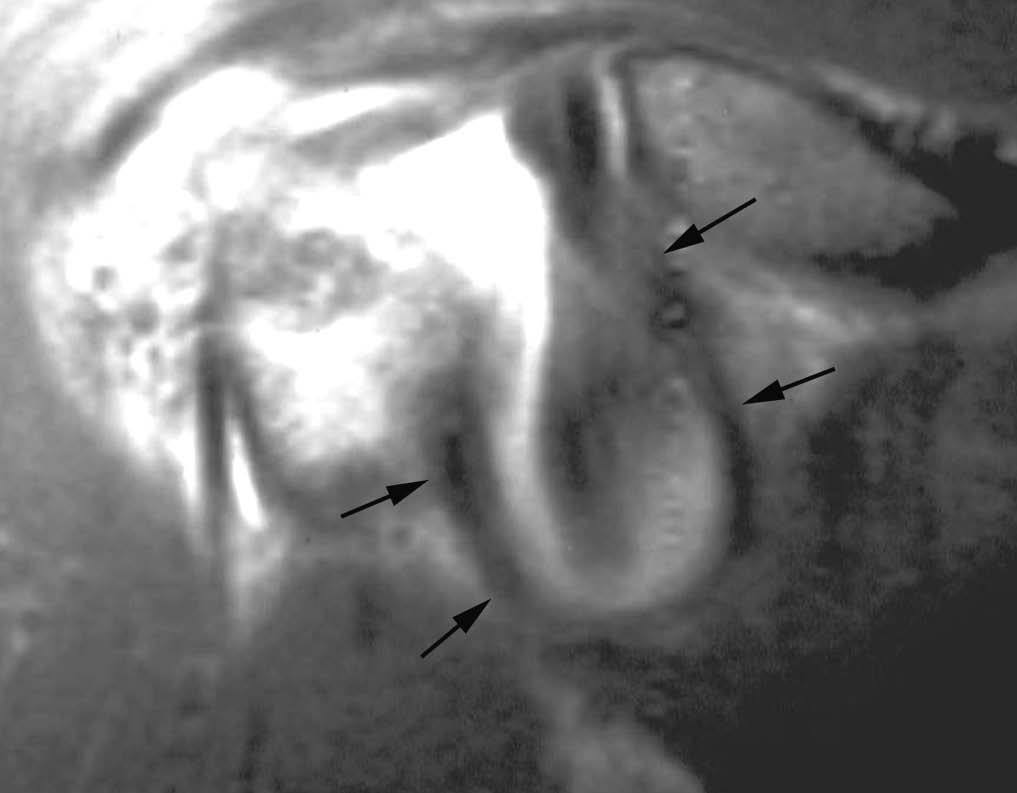

SLAP III: en este tipo existe un desprendimiento del LG superior hacia la cabeza articular, semejante a una rotura en asa de cubo en el menisco de la rodilla (fig. 24).

Fig. 24.--SLAP (superior labrum anterior posterior) tipo III. Dibujo esquemático (A) y artrorresonancia coronal oblicua T1 con supresión grasa (B) que ilustran una rotura parcial del labio glenoideo superior con desplazamiento inferior de un fragmento de labio glenoideo (flecha en B), semejante a una rotura en asa de cubo del menisco.